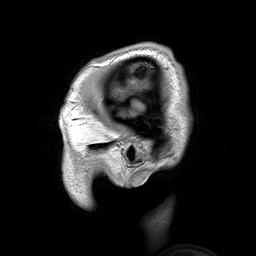

- Magnetic resonance imaging (MRI), including functional magnetic resonance imaging (fMRI) and other methods for functional neuroimaging of the brain.

- For example, nuclear magnetic resonance (often referred to as magnetic resonance imaging to avoid the common concerns about radiation), uses the phenomenon of nuclear resonance to image the human body.